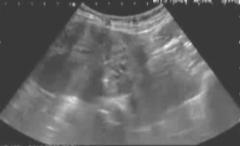

子宫腺肌症客观疗效

38 岁 典型症状,经期大出血和痛经 结合带增宽,典型子宫腺肌症MRI表现 血管造影表现 子宫肌瘤相同的栓塞技术,双侧股动脉穿刺,双侧子宫动脉插管,子宫肌瘤栓塞相同的栓塞剂,注意栓塞终点 100%子宫腺肌症梗死,子宫容积减少40%...[查看全文]